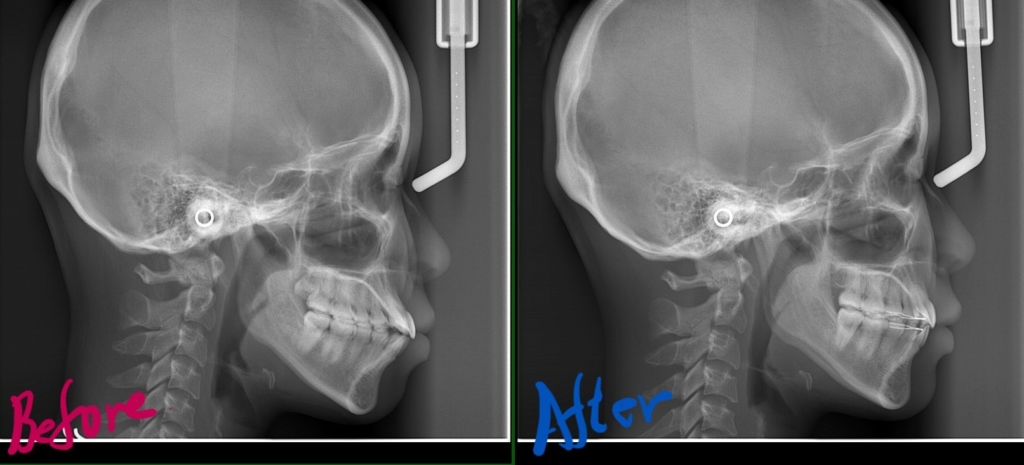

参考までに、矯正治療の前後を比較してみましょう。

まずは、横顔と口元の比較です。

左側が矯正治療前、右側が矯正治療後

レントゲン写真でも比較してみましょう